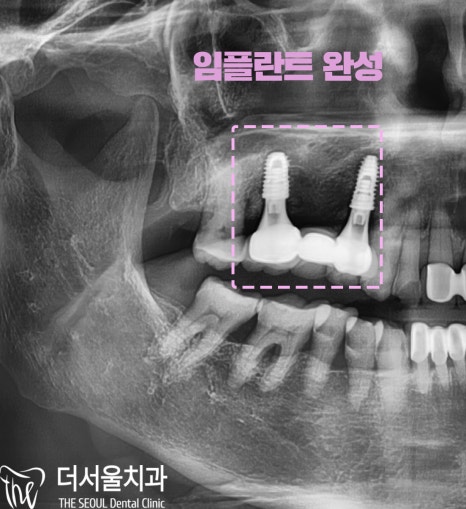

최종적으로 완성된 모습입니다^^

오늘은

어금니 뿌리[ 치근 ]이 부러진 관계로

임플란트를 심었던 사례를 설명해 드렸습니다.